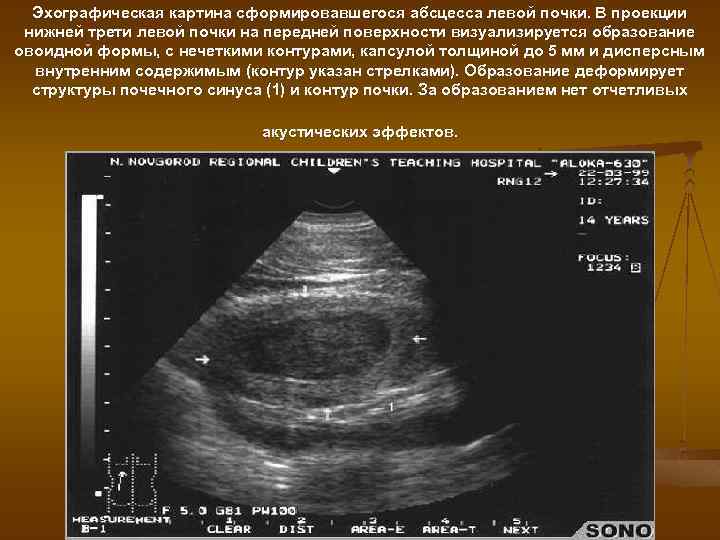

Эхографическая картина сформировавшегося абсцесса левой почки. В проекции нижней трети левой почки на передней поверхности визуализируется образование овоидной формы, с нечеткими контурами, капсулой толщиной до 5 мм и дисперсным внутренним содержимым (контур указан стрелками). Образование деформирует структуры почечного синуса (1) и контур почки. За образованием нет отчетливых акустических эффектов.